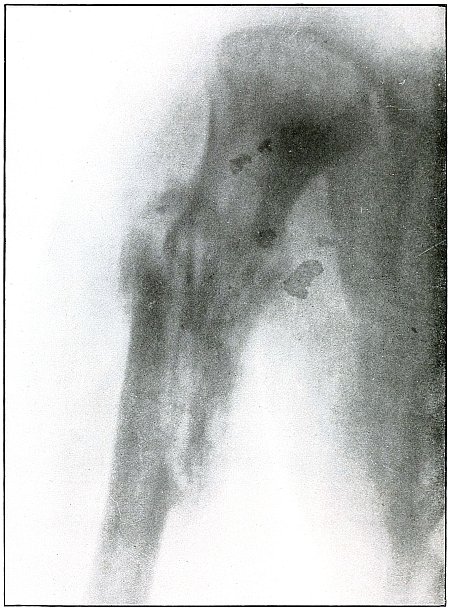

Gunshot fracture, humerus |

192 |

| 92. |

Gunshot fracture, humerus |

194 |

| 93. |

Gunshot fracture, humerus |

196 |